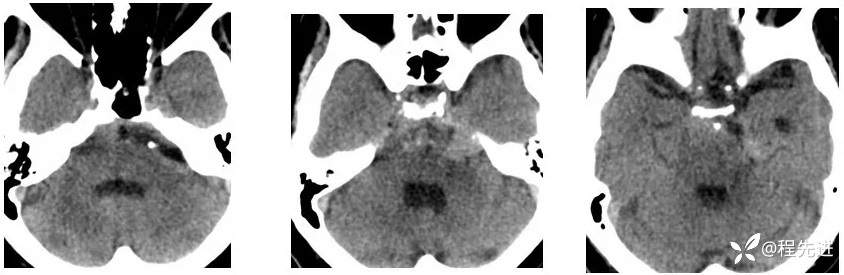

【现病史及既往史】:右眼斜视及视力下降7个月,右眼脸下垂3个月,右眼失明1个月

查体:生命体征平稳,右眼脸下垂,右眼失明,左眼内收位,外展受限,光反应迟钝,左侧角膜反射减弱,左侧听力下降,左面部痛温觉减弱无吞咽困难,无饮食饮水呛咳,伸舌舌尖左偏。